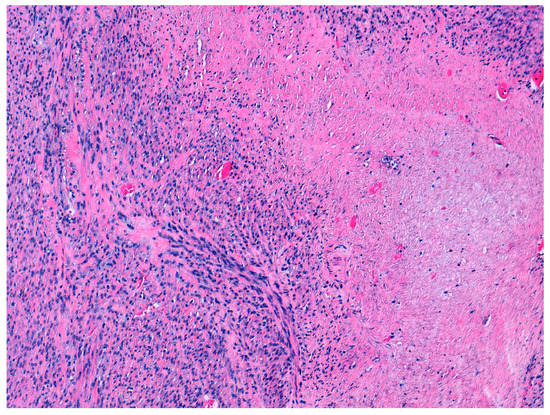

According to the 2014 WHO criteria [9], the pathological diagnosis of STUMP is based on the presence of coagulative necrosis (cases 1 and 4), the finding of 24 mitoses per field and moderate focal atypia (case 2), and diffuse moderate atypia (case 3) (Figure 1 and Figure 2).

Figure 1.

Hematoxilin and eosin staining (10×). Focal cell necrosis. Case 1.

Figure 2.

Hematoxilin and eosin staining (40×). Cytological atypia. Case 2.